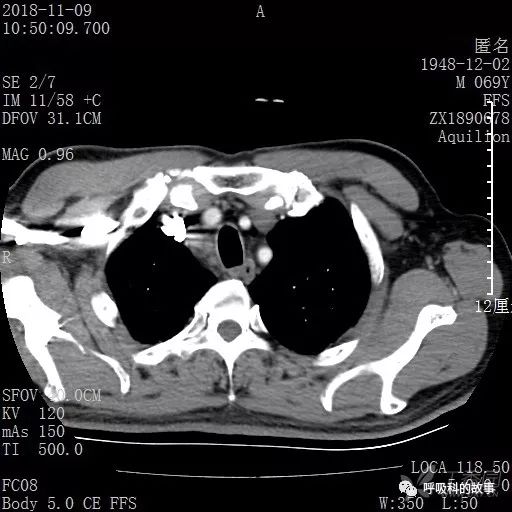

胸部增强CT示右肺门占位伴远端阻塞性肺炎,纵膈、右肺门、右侧颈根部、右侧腋下及肝门部肿大淋巴结。两侧胸腔少量积液。

纵隔窗的增强CT